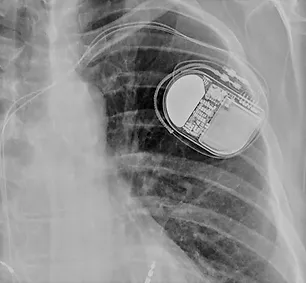

Ο βηματοδότης αποτελείται από τη γεννήτρια η οποία τοποθετείται υποδόρια (συνήθως στο αριστερό άνω ημιθωράκιο) και ένα ή δύο ηλεκτρόδια ανάλογα με το αν είναι μονοεστιακός ή διπλοεστιακός.